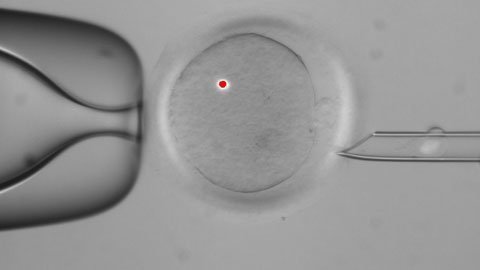

Theo thông báo mới nhất của các nhà khoa học Oregon, họ đã tạo ra khoảng hơn 12 phôi thai người ở giai đoạn đầu và phát hiện, kỹ thuật này rất hiệu quả trong việc thay thế ADN. Tuy nhiên, các gen mà họ muốn thay thế không phải được tìm thấy trong nhân của tế bào và ảnh hưởng tới các đặc điểm thể chất như màu mắt và chiều cao. Thay vào đó, các gen thay thế nằm ngoài nhân tế bào, trong một cấu trúc sản sinh năng lượng có tên gọi l mitochondria. Những gen này chỉ di truyền từ mẹ, chứ không phải từ bố.

Kỹ thuật mới, nếu được phê chuẩn sử dụng, sẽ cho phép một phụ nữ sinh con thừa hưởng các nhân ADN của cô nhưng mitochondrial ADN của một phụ nữ khác hiến tặng. "Đây có thể là phương pháp tốt nhất để chống lại các căn bệnh di truyền nan y do lỗi gen mitochondria.